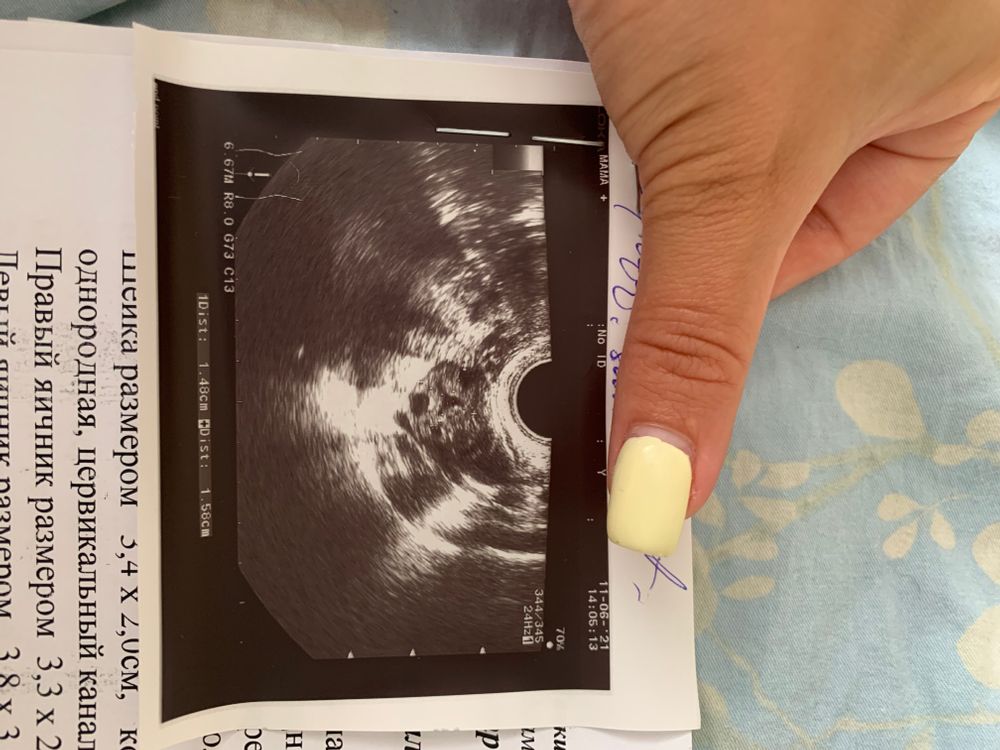

Всем привет. Можно ли ли по узи органов малого таза увидеть спаечный процесс?? Сегодня гинеколог сказала: другие может и не видят, а я увижу. Смотрю на узи и кажется там все в спайках((( нагоняю на себя. Страшно. Посмотрите☹️ самое страшное для себя услышать трубы непроходимы - только эко .

Вы анимии и витамины проверяли? Гормоны половые, щитовидной. Ну овуля получается есть, на узи ДФ 17мм в левом Я? Эндик всегда норм? Полипов, кист не находят? Циклы регулярные?